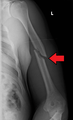

A fracture of the greater tubercle as seen on AP X ray

A fracture of the greater tubercle of the humerus

Fracture of the greater tubercle of the humerus

Fracture of the proximal humerus with involvement of the greater tubercle